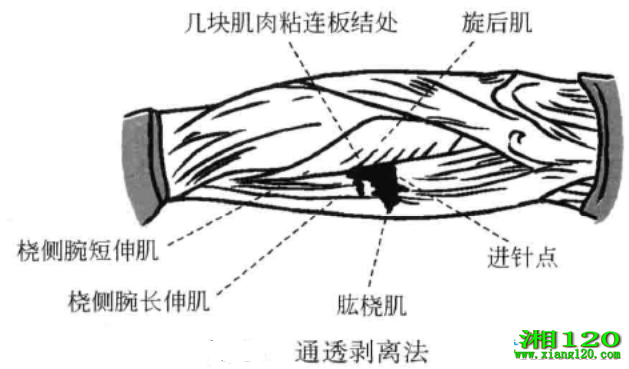

3、通透剥离法

当某处有范闱较大的粘连板结,无法进行逐点剥离时,在板结处可以取数个进针点,进针点都选在肌肉和肌肉或其他软组织相邻的间隙处,当刀口接触到骨面时,除软组织在骨伤的附着点之外,都将软组织从骨面上铲起,并尽可能将软组织互相之间的粘连疏剥开,将结瘢切开。